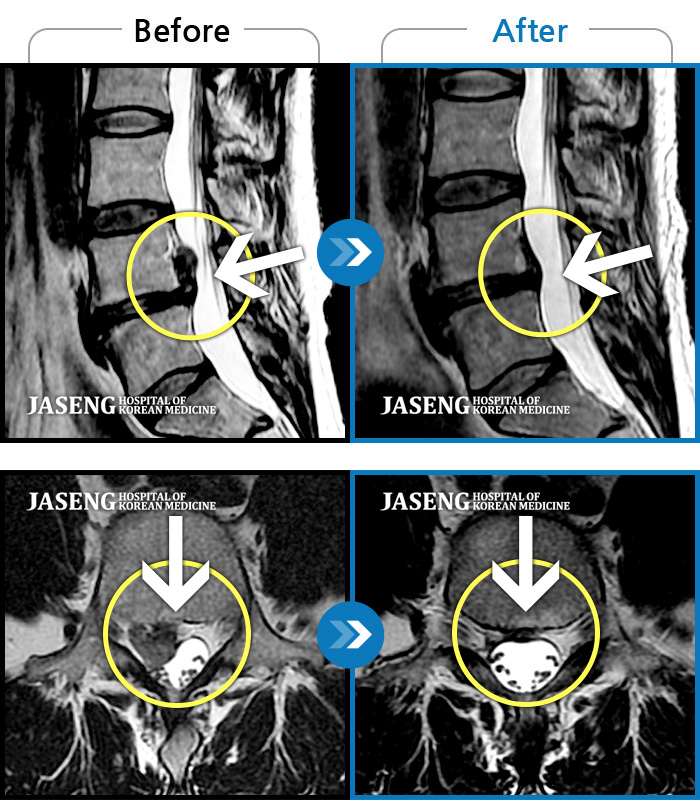

[뱸] 19.11.28~25.05.06

ȯںп Ǹ ǿ ԿǾ, ο ġ ۿ Ƿ ġḦ Ͻñ ٶϴ.